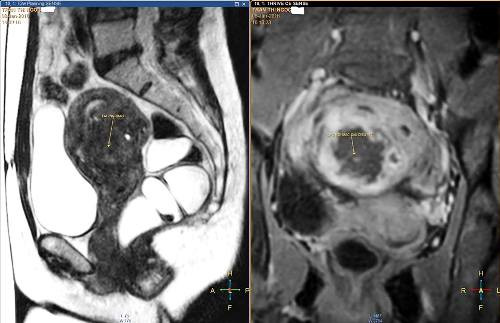

| Ảnh MRI khốilạc nội mạc tử cung của chị Kim. |